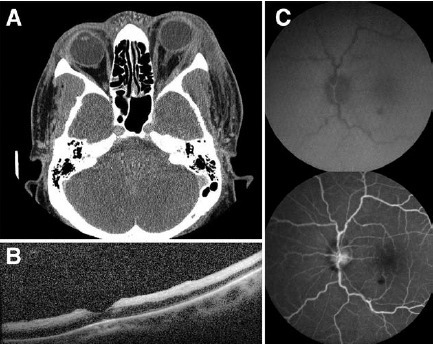

图 2 为 CT 和眼底像图。A 为轴位平扫 CT 显示左眼外侧眶高密度区,并向前扩展;B 为光学相干断层扫描(OCT),可见内层视网膜的损伤显示视网膜缺血;C 为眼底荧光血管造影(FFA),上图为 47 秒图,下图为 4 分 41 秒图,均显示充盈迟缓

左眼外眼皮肤脱屑、坏死,眼睑水肿、淤血,睑缘可见脓性分泌物。裂隙灯检查示左眼弥漫性球结膜水肿、充血。眼底检查显示左眼视网膜缺血,可见樱桃红斑、视乳头水肿、静脉迂曲扩张以及视网膜出血。细菌培养显示革兰阳性球菌生长。以眶蜂窝织炎治疗,患者开始静点万古霉素和他巴唑坦。眼眶 CT 显示眶脂肪没有窦道。FFA 显示动脉充盈延迟以及视神经染色。